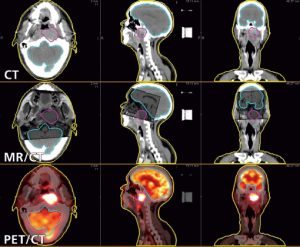

Deforme Edilebilir PET/CT | En İyi PET Hedef Hacim Konturlama

İlk PET/CT hizalama işleminden GTV’lerin konturlanmasına kadar tüm işlerde MIM Maestro, PET görüntülerini tedavi planlama CT’leriyle birleştirmek için bir çözüm sunmaktadır. MIM için üretilen PET Edge™ aracı, PET ağır lezyonları doğru ve istikrarlı konturlamaktadır.

PET Edge, gradiyene dayalı bir tekniktir. PET aktivitesindeki en dik inişi saptayarak kontur sınırını otomatik oluşturur ve genel eşik tekniğine kıyasla istatistik açısından daha doğru olmasını sağlar. Bu araç, görsel kontrast ne olursa olsun PET görüntüleri üzerine tümör hacimlerini çizerken istikrarlı sonuçlar elde edilmesini sağlar.